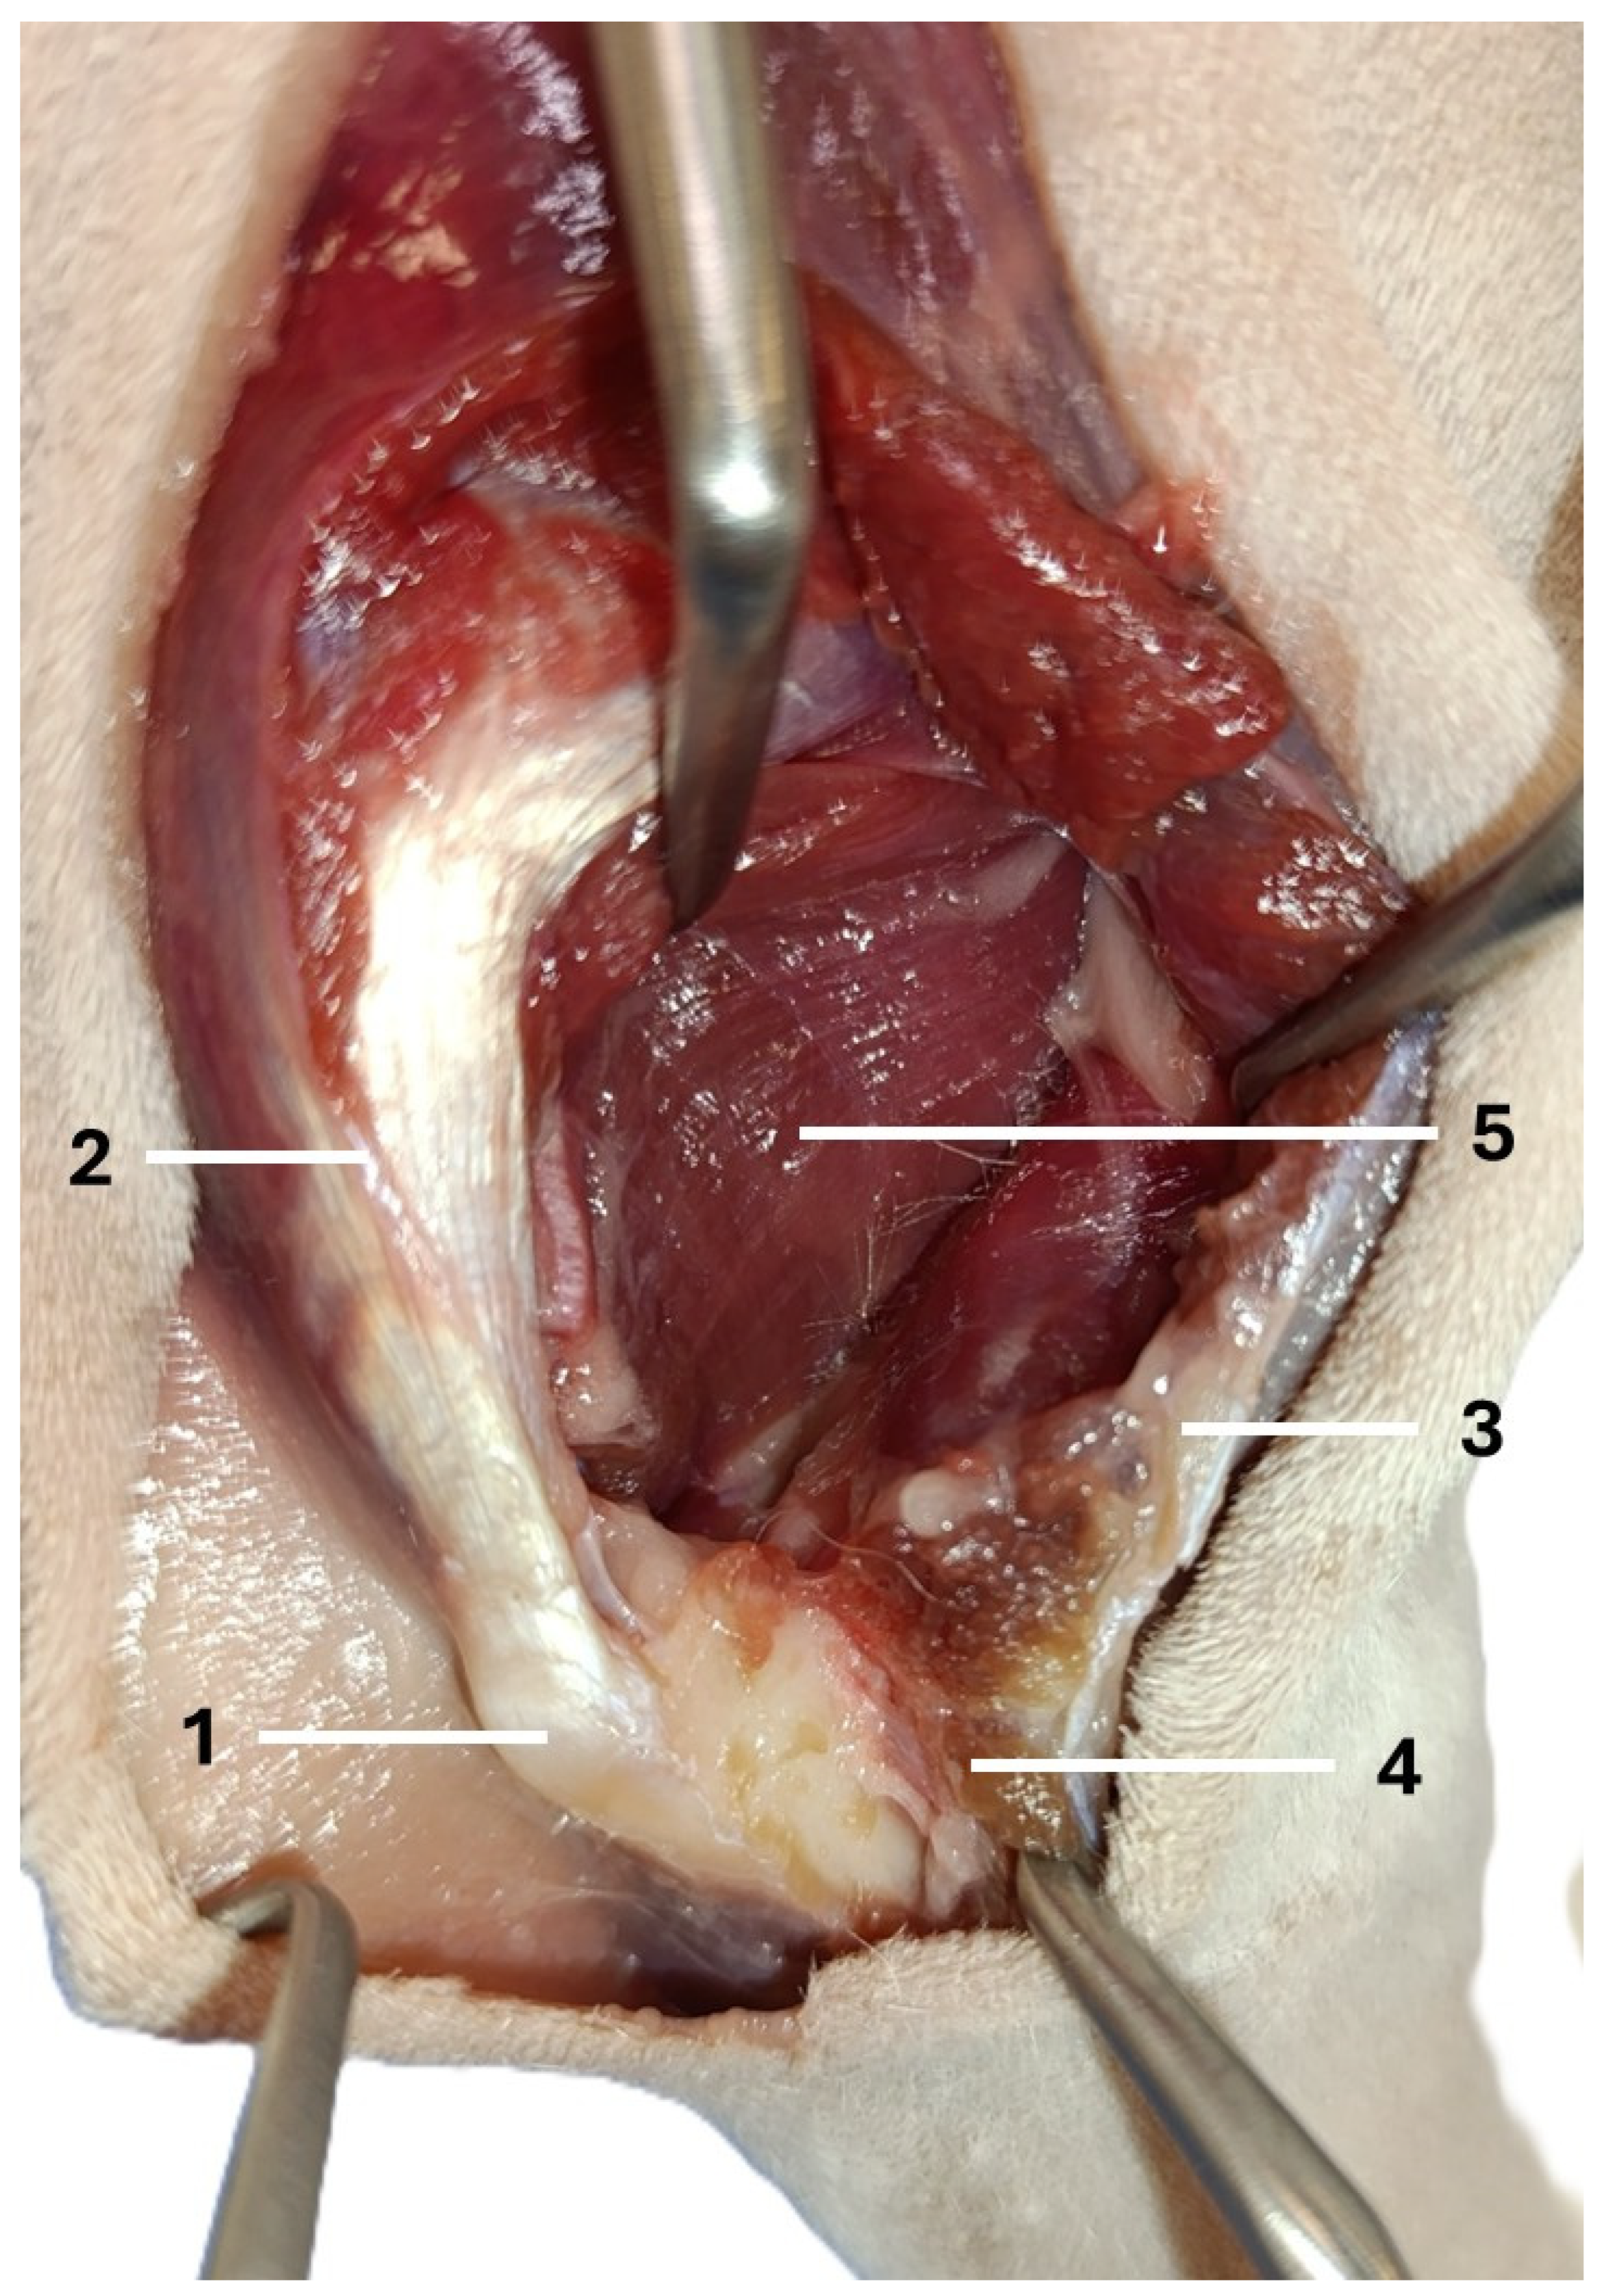

An Anatomical Study on Canine Cadavers Investigating the Caudolateral Approach Involving the Elevation of the Anconeus Muscle and Splitting of the Triceps Brachii Muscle for the Potential Treatment of T-Y Humeral Fractures

Trębacz, P.; Frymus, J.; Czopowicz, M.; Barteczko, A.; Pawlik, M.; Kurkowska, A. An Anatomical Study on Canine Cadavers Investigating the Caudolateral Approach Involving the Elevation of the Anconeus Muscle and Splitting of the Triceps Brachii Muscle for the Potential Treatment of T-Y Humeral Fractures. Animals 2026, 16, 110. https://doi.org/10.3390/ani16010110